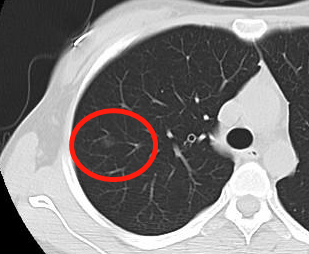

现在胸部X线和CT检查是诊断胸部疾病最常用的手段。胸部CT体检中肺部小结节的发生率高达约10%-20%,发现率远高于X线检查。由于CT具有X线无法比拟的优势,它具有高分辨力,并且为横断位图像,可以避免肋骨、脊柱、心脏的阻挡而清晰的观察肺组织。X线胸片敏感性则相对较差,发现肺癌多数已经中晚期,并常有假阳性,约有30%左右X线胸片报告的肺部结节为假阳性,即没有病灶而是伪影。放射科诊断医师主要是根据小结节的大小、形态、密度、有无钙化、周围有无卫星病灶,边缘有无分叶、毛刺、胸膜凹陷等情况来判断小结节的良恶性,目前诊断准确率可达到95%以上,胸部CT目前被公认为是诊断肺部小结节的最佳检查手段。

对于大于1cm的结节应当尽量通过多种方法确定结节的良恶性。直径大于1cm的肺内单发小结节,恶性的占到一半以上,而小于5mm的微小结节,如果没有肿瘤病史,则90%以上为良性结节,因此,5mm以下的肺结节每6个月作CT复查一次就可以;5-10mm的肺结节应每3个月作CT复查一次;10mm的肺结节应每1~2个月作CT复查一次。如果随访发现病灶无变化,则常延长至3个月、6个月、1年进行复查,如发现肺小结节2年无变化,则可大致认为为良性结节。当发现病灶有变化时,则根据变化情况作出判断并决定下一步处理意见。

由于近年来螺旋CT的发展迅速,能被发现的小结节越来越多,小于2毫米的肺小结节都能给发现,这加大了医生诊断的难度,同时也给患者是否接受治疗带来一定的困扰。